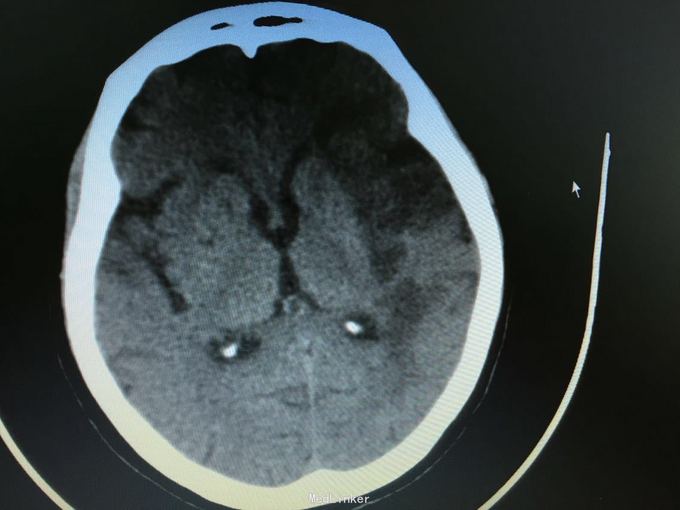

主诉:突发左侧肢体无力伴意识障碍2.5小时。 现病史:患者于2.5小时前突发左侧肢体无力,左侧肢体完全不能动,伴有意识障碍,急诊头CT显示多发脑梗死,为进一步诊治入院。 既往史:高血压,冠心病支架后,阵发房颤。

昏睡,完全混合性失语,双眼向左侧凝视,右侧肢体肌力0级,右侧病理征阳性。 头CT见多发陈旧小梗死。

目前住院10余天,意识清楚,但仍遗留左侧肢体肌力0级,混合性失语等严重功能残疾。复查CT显示为左侧大脑半球大面积脑梗死。 讨论:对于高龄,大面积脑梗死患者,时间窗内是否溶栓?静脉还是动脉溶栓?